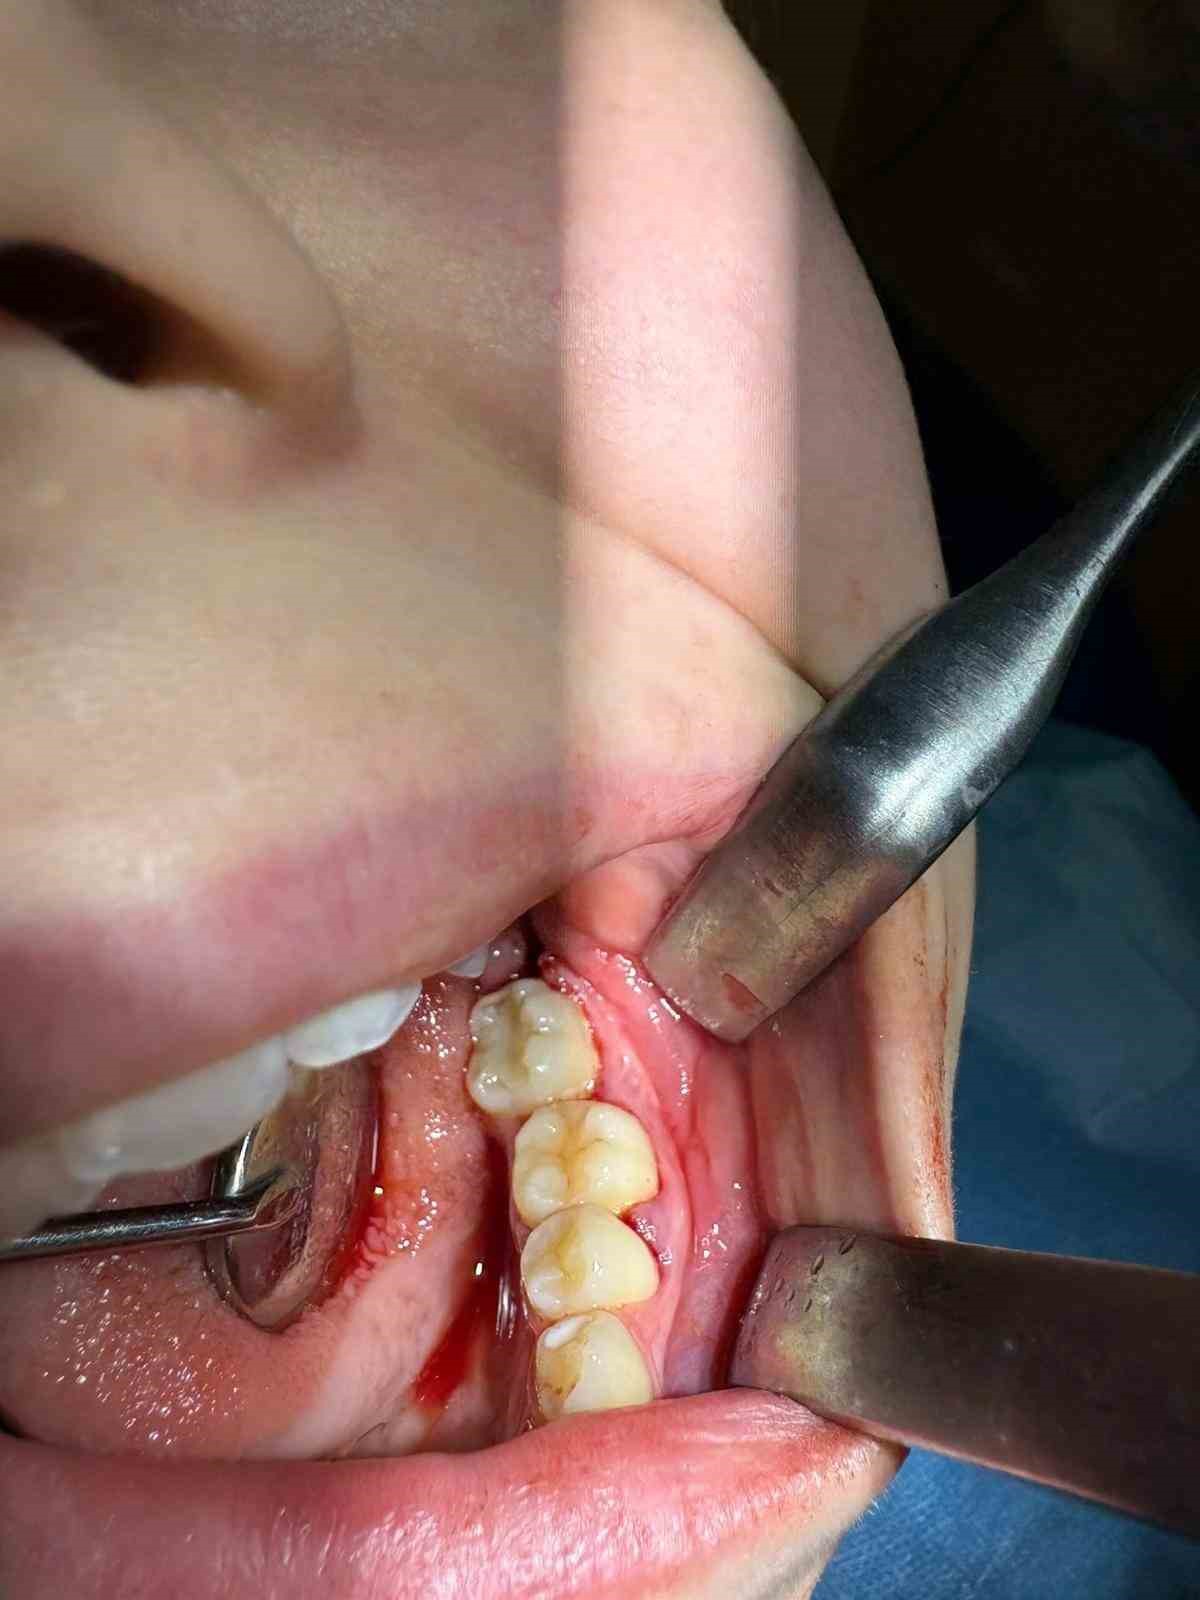

İleri düzey çürük nedeniyle daimi azı dişi çekilen hastaya, yaşı gereği çene gelişimi devam ettiği için klasik implant tedavisi uygun görülmedi. Bunun yerine, hastanın ağzında gömülü halde bulunan yirmi yaş dişi, uzman ekip tarafından cerrahi operasyonla çıkarılarak çekilen dişin yerine nakledildi.

Operasyon sırasında, dişin sağlıklı bir şekilde tutunmasını sağlamak için hastanın kendi kanından elde edilen PRF (Platelet Rich Fibrin) materyali, nakil öncesi hazırlanan diş yuvasına yerleştirildi. Bu uygulama, doku iyileşmesini hızlandıran ve hücre yenilenmesini destekleyen doğal bir yöntem olarak öne çıkıyor. Bu tedavi yöntemi, hastanın kendi dişi kullanıldığı için doğal görünüm, uyum ve fonksiyon açısından büyük avantaj sağlıyor. Aynı zamanda, vücut tarafından kabul edilme oranı yüksek olduğundan, uzun vadeli başarı şansı da oldukça yüksek.